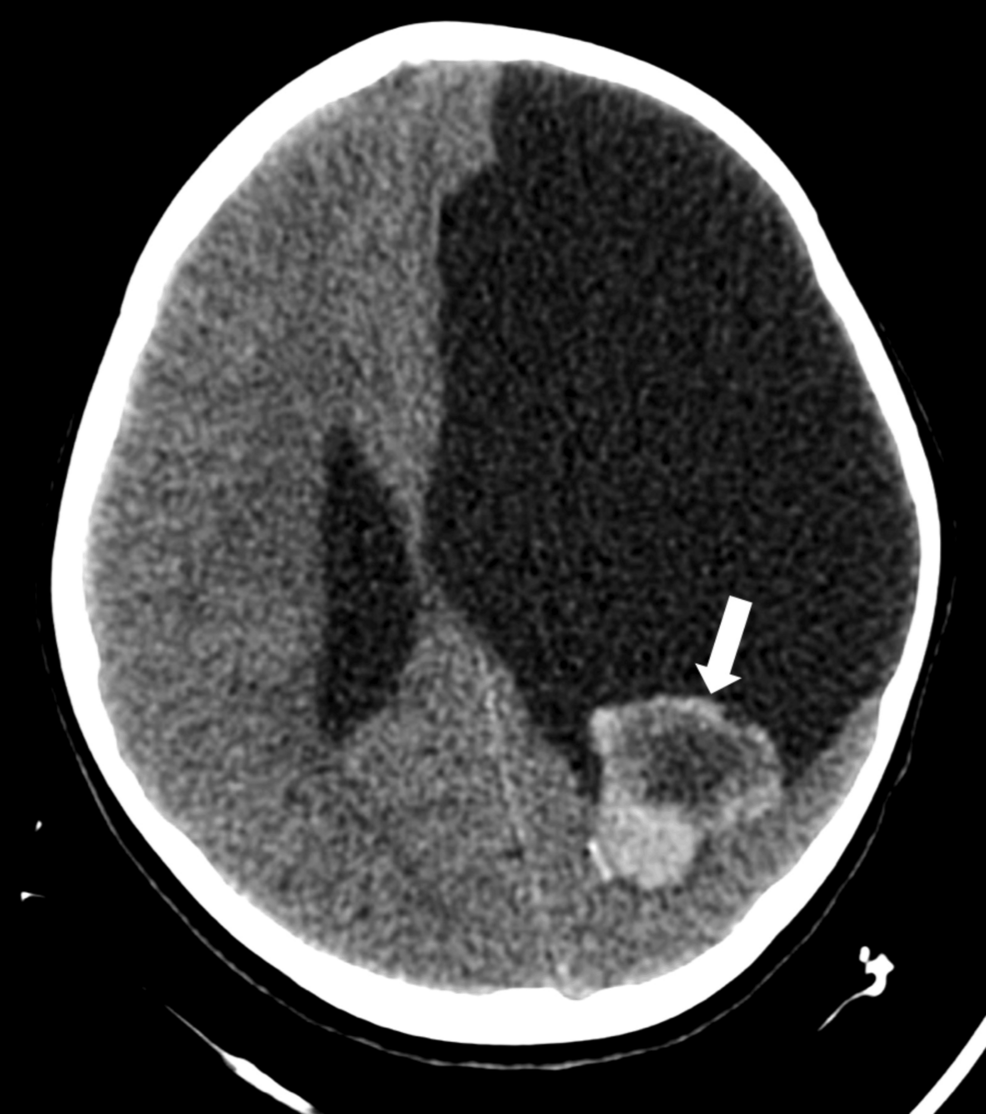

When an intracranial hemorrhage presents initially, it may appear as a brain tumor for several reasons. The mass effect caused by blood accumulation, along with associated edema, can mimic the space-occupying properties of a true neoplasm. Additionally, patients often exhibit similar symptoms such as headaches, focal neurological deficits, seizures, and vomiting. The clinical presentation will vary depending on the location and size of the hemorrhage and the child’s developmental stage.

Misdiagnosis of a hemorrhage with this presentation can occur without rapid and accurate imaging and understanding of the patient’s clinical history, notably concerning predisposition to HHT.

The image below details common techniques used to differentiate ICH from Neoplasm.

| Diagnostic Tool | ICH Findings | Neoplasm Findings |

|---|---|---|

| CT Scan (Computed Tomography) | Hyperdense (bright) blood, mass effect, possibly edema. | Variable density,often with mass effect and edema; may show calcifications or contrast enhancement. |

| MRI (Magnetic Resonance Imaging) | Blood shows characteristic signal changes over time (stages of blood degradation). May reveal AVMs. | Variable signal intensity, often with contrast enhancement; detailed anatomical visualization. |

| Angiography (Digital Subtraction angiography – DSA) | may reveal AVMs or other vascular abnormalities, source of hemorrhage. | May show tumor vascularity or vessel displacement. |